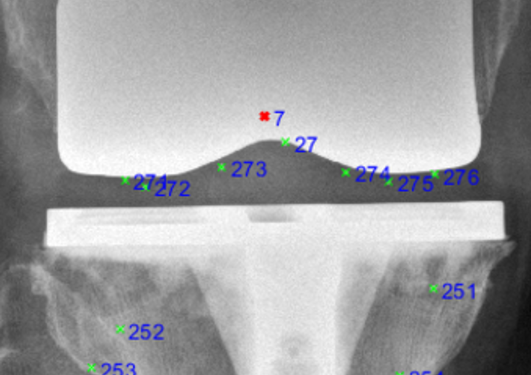

The laboratory-based testing methods include chemical analysis, physico-chemical characterization, biomechanical characterization and simulation, radiostereometric analysis, cell culture studies as well as analyses of retrieved materials and tissue, which establish the link to clinical research and registry studies.